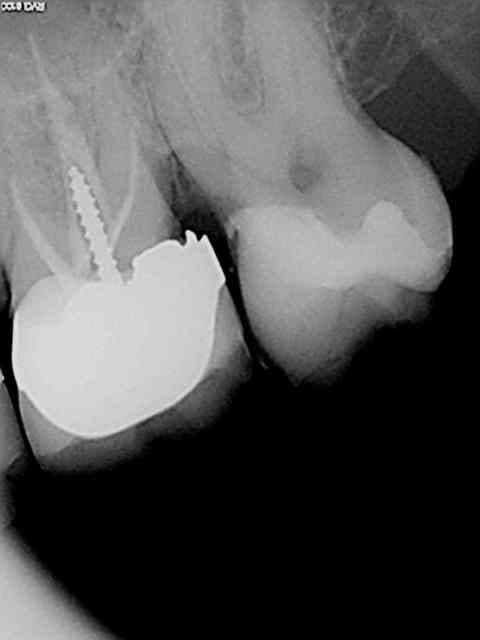

Exemple concret, de ce samedi (exceptionnellement au boulot car c'est un pote qui travaille sur Paris et qui a une semaine de vacances), j'en ai tous les jours.

la première radio date de 2011 issue d'un status inutile selon la sécu. Suspicion de reprise en mésial sous l'onlay de 27, noté sur le dossier à surveiller. Le patient appelle pour douleurs lancinantes spontanées la semaine dernière en haut au fond et à gauche exacerbées par le froid.

Diagnostic clair net et précis et par téléphone en plus : ca n'est pas du au tt merdique de la 26. Ce qui est confirmé in situ par la radio numéro 2 prise le jour meme de l'endo.

Comme à mon habitude je m'excuse d'avoir irradié le patient copieusement ( à raison de 70 kv et 0,099 s par cliché) plutot qu'un seul cliché argentique en fin de tt ( 70 kv aussi mais 1,3 s d'exposition lui) développé en fin de journée comme ca a du etre le cas pour le tt de 26 ( et m... encore raté).

Je sais pas moi mais le résultat parle de lui meme ( putain de mv2 que j'ai réussi à choper dans un 2 eme temps une fois les autres obturés)

Taille empreinte provisoire dans la foulée , l'avantage de la gutta chaude.

Vous préférez quoi dans votre bouche ? une seule radio et un tt endo comme la 26 ou 6 clichés et mon tt endo de 27 ?